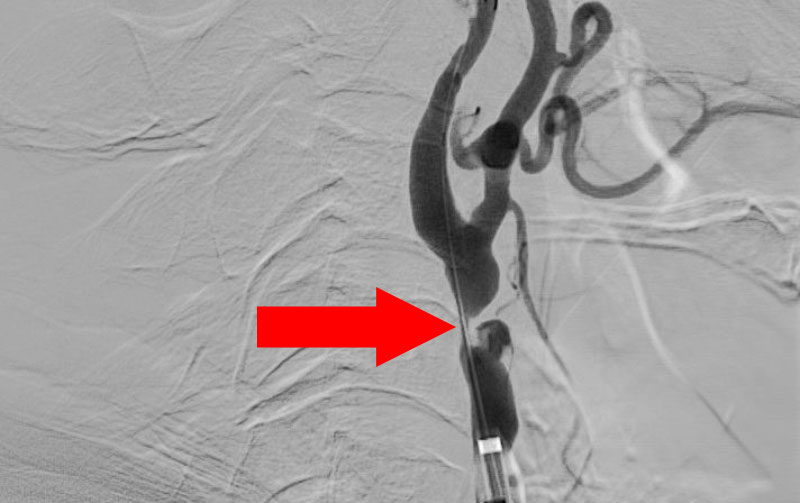

No.1377 手術前

No.1377 手術中

No.1377 手術後